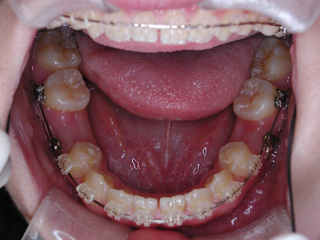

この症例では、目的外使用のオーソアンカー SMAPシステム が用いられています。

使用した主な装置名:マルチブラケット装置、オーソアンカー SMAPシステム

下顎の第二小臼歯の先天欠如が見られました。先天性欠如歯がある場合、上下顎小臼歯抜歯のスタイルで歯数を合わせる事も多いのですが、抜歯数が増えるのが難点です。 プロファイル、下顎前突、非対称の問題を考慮して下顎にオーソアンカー SMAPシステム を植立し、下顎晩期残存の乳歯のみを抜歯し、永久歯の抜歯は行わず空隙を閉鎖致しました。大臼歯の咬合についてはIII 級仕上げ という噛み合わせにしています。